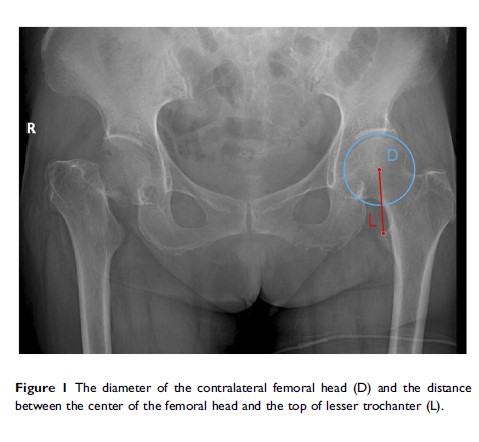

一种减小半髋关节置换术后下肢不等长的简单方法